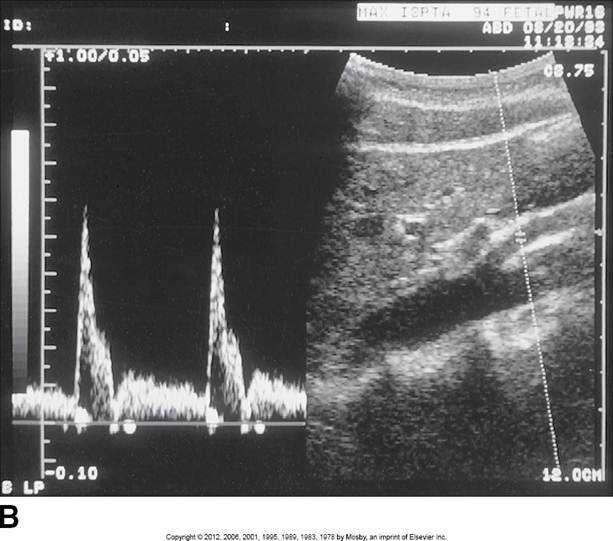

Proximal aorta

High systolic peak

Low diastolic comp.

Clean window